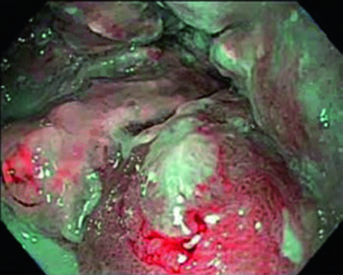

Physicians should delineate the GTV with reference to CT and PET imaging, as well as findings on upper endoscopy and endoscopic ultrasound (EUS). EUS is particularly valuable for staging tumor invasion depth and classifying small periesophageal lymph nodes that are difficult to assess by CT or PET alone. If the tumor is superior to the carina, bronchoscopy is recommended to rule out tracheoesophageal fistula, which may delay radiotherapy.

The following cases, drawn directly from the textbook, illustrate the practical application of these guidelines in real-world scenarios. Each case demonstrates how to integrate PET, endoscopy, and EUS findings into volume contouring.

Case 1: Cervical/Upper Thoracic SCC — 69-Year-Old

A 69-year-old patient with SCC of the cervical/upper thoracic esophagus. PET-CT revealed FDG-avid primary and mildly avid paratracheal lymph nodes. EGD showed an ulcerating submucosal mass 15–23 cm from the incisors. Delineated volumes included: brachial plexus (purple), larynx (yellow), esophageal GTV (red), nodal GTV (green), CTV (orange), PTV 54 Gy (cyan), and PTV 60 Gy (dark blue). The superior border of the supraclavicular field was placed at the inferior border of the cricoid cartilage, with bilateral elective SCV nodal coverage.